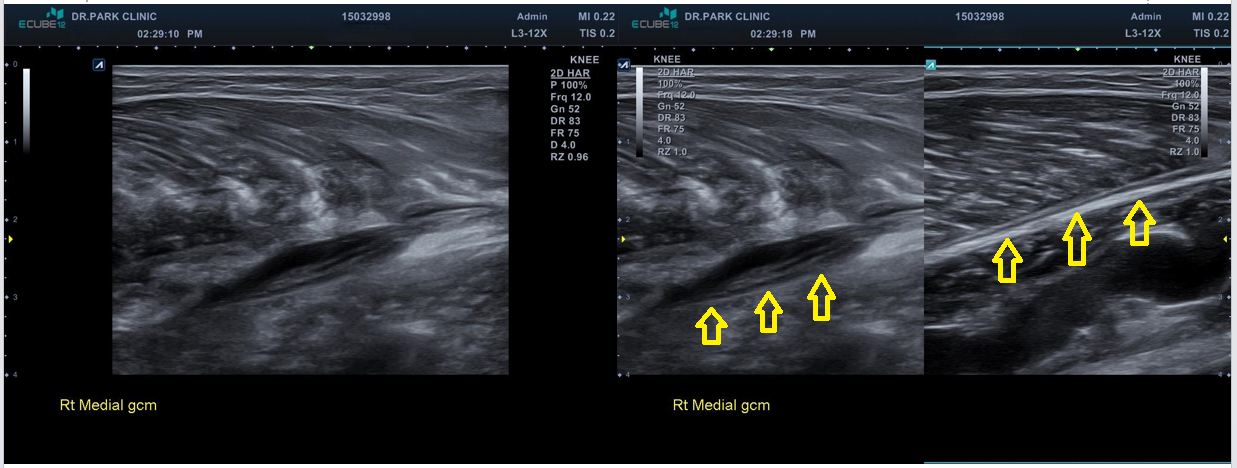

초음파 검사를 하니 근육 파열을 더 자세히 확인할 수 있습니다. 근육은 각각 근막으로 둘러쌓여 있고 이게 근육과 근육을 얇게 구분해주고 있는데요, 근육이 찢어지면 보통 이 근막이 벌어지게 됩니다. 이 환자분도 근막이 벌어지는 근육파열 양상을 보이고 있습니다